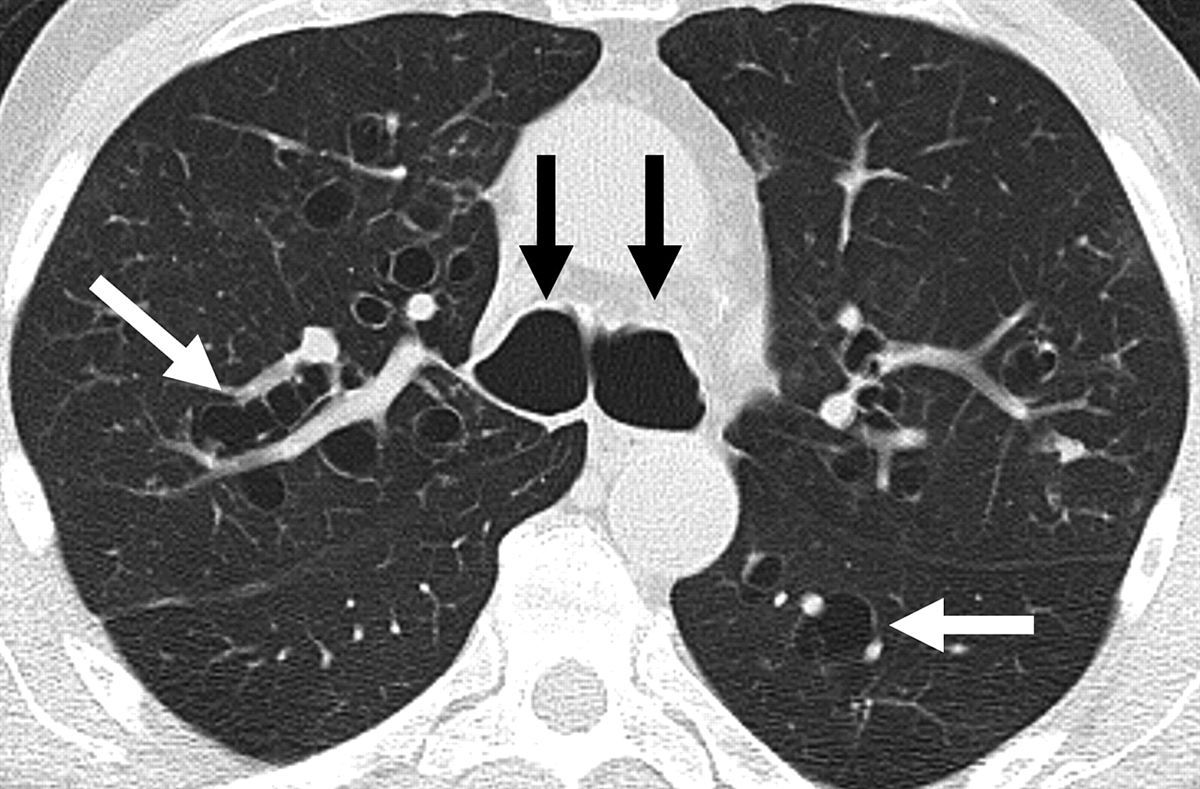

Impact of Different Etiologies of Bronchiectasis on the Pulmonary

From www.clinmedres.org

Impact of Different Etiologies of Bronchiectasis on the Pulmonary Gold Standard Test For Bronchiectasis To determine whether airways are dilated, airway diameters are. This version is written for patients and the public to help you understand what was recommended in the original guideline. It represents the gold standard in terms of quality of care for people with adult bronchiectasis in europe, and can be used as an educational resource for healthcare professionals. Chest computed. Gold Standard Test For Bronchiectasis.